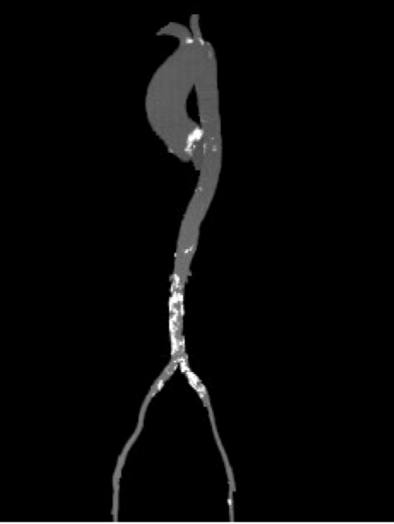

外周血管及主动脉弓解剖

双侧血管内径良好,所见腹主动脉血管壁钙化形成